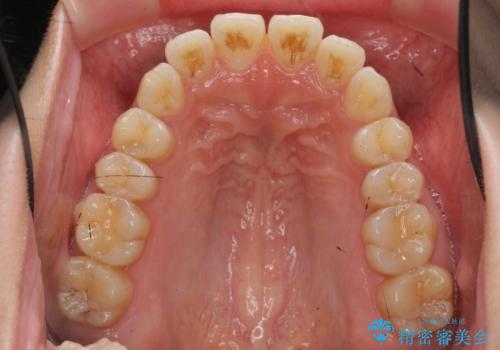

- 前歯の噛み合わせの開きの改善を求めて来院されました。

奥歯はほとんど動かさず(奥歯の噛み合わせはほとんど変えず)前歯のIPR矯正でガタつき前突感(出っ歯感)の改善を計画します。

ほとんど前歯のみの矯正治療であることからトータル14枚のマウスピースで並べるインビザラインライトによる治療を行います。